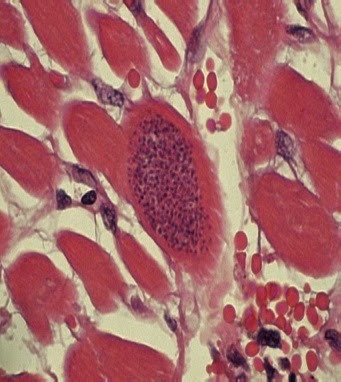

Descubrió el núcleo celular en los organismos eucariotas. En 1827, examinando granos de polen, esporas de musgos, y Equisetum suspendidos en agua, al microscopio, Brown observó diminutas partículas con vacuolas en los granos de polen ejecutando un continuo movimiento aleatorio. Luego lo corrobora al mismo movimiento en partículas de polvo, anulando su anterior hipótesis que el movimiento se debía a que el polen tenía vida.